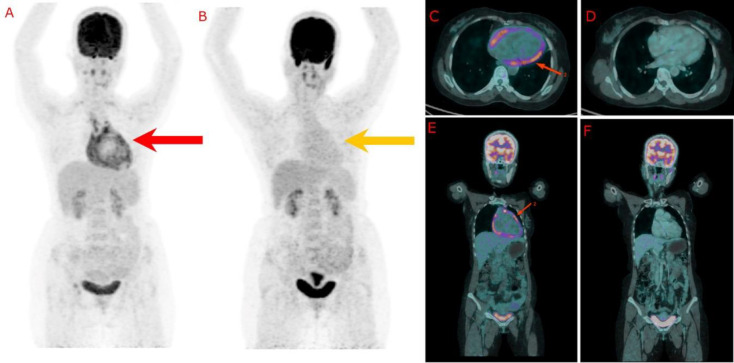

Tuberculous pericarditis (TBP) is a rare but potentially life-threatening manifestation of tuberculosis, often presenting with nonspecific symptoms and varied clinical features. The disease is characterised by inflammation of the pericardium due to mycobacterium tuberculosis, leading to complications such as effusion, tamponade, and, in chronic cases, constrictive pericarditis. TBP is associated with high mortality, particularly if not promptly diagnosed and treated. 18F-fluorodeoxyglucose positron emission tomography-computed tomography (18FDG PET-CT) has proven invaluable in diagnosing and managing TBP. This imaging modality allows for precise inflammatory activity localisation and differentiates TBP from other causes of pericardial disease. Additionally, the cardiac inflammation protocol of 18FDG PET-CT enhances imaging accuracy by suppressing the normal physiological FDG uptake in the myocardium. In this case report, we highlight the pivotal role of the cardiac inflammation protocol of 18FDG PET-CT in both the initial diagnosis and subsequent response assessment of TBP, underscoring its importance in clinical practice.